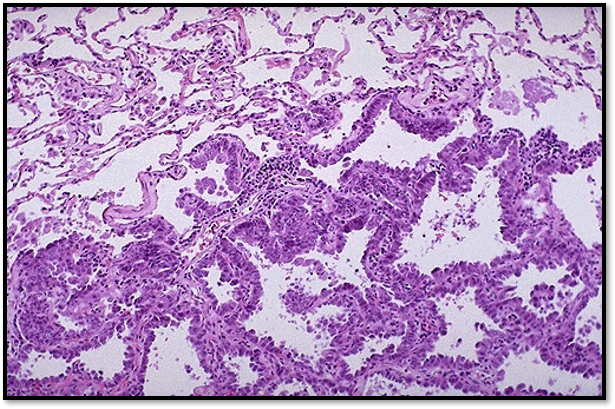

Where do the tumor cells grow in bronchioloalveolar carcinoma?

along the walls of pre existing alveoli – lepidic pattern

central tumor

organoid, trabecular, palisading, ribbon, or rosette-like arrangements of cells separated by a delicate fibrovascular stroma

Electron microscopy shows dense core granules

Carcinoid Tumor